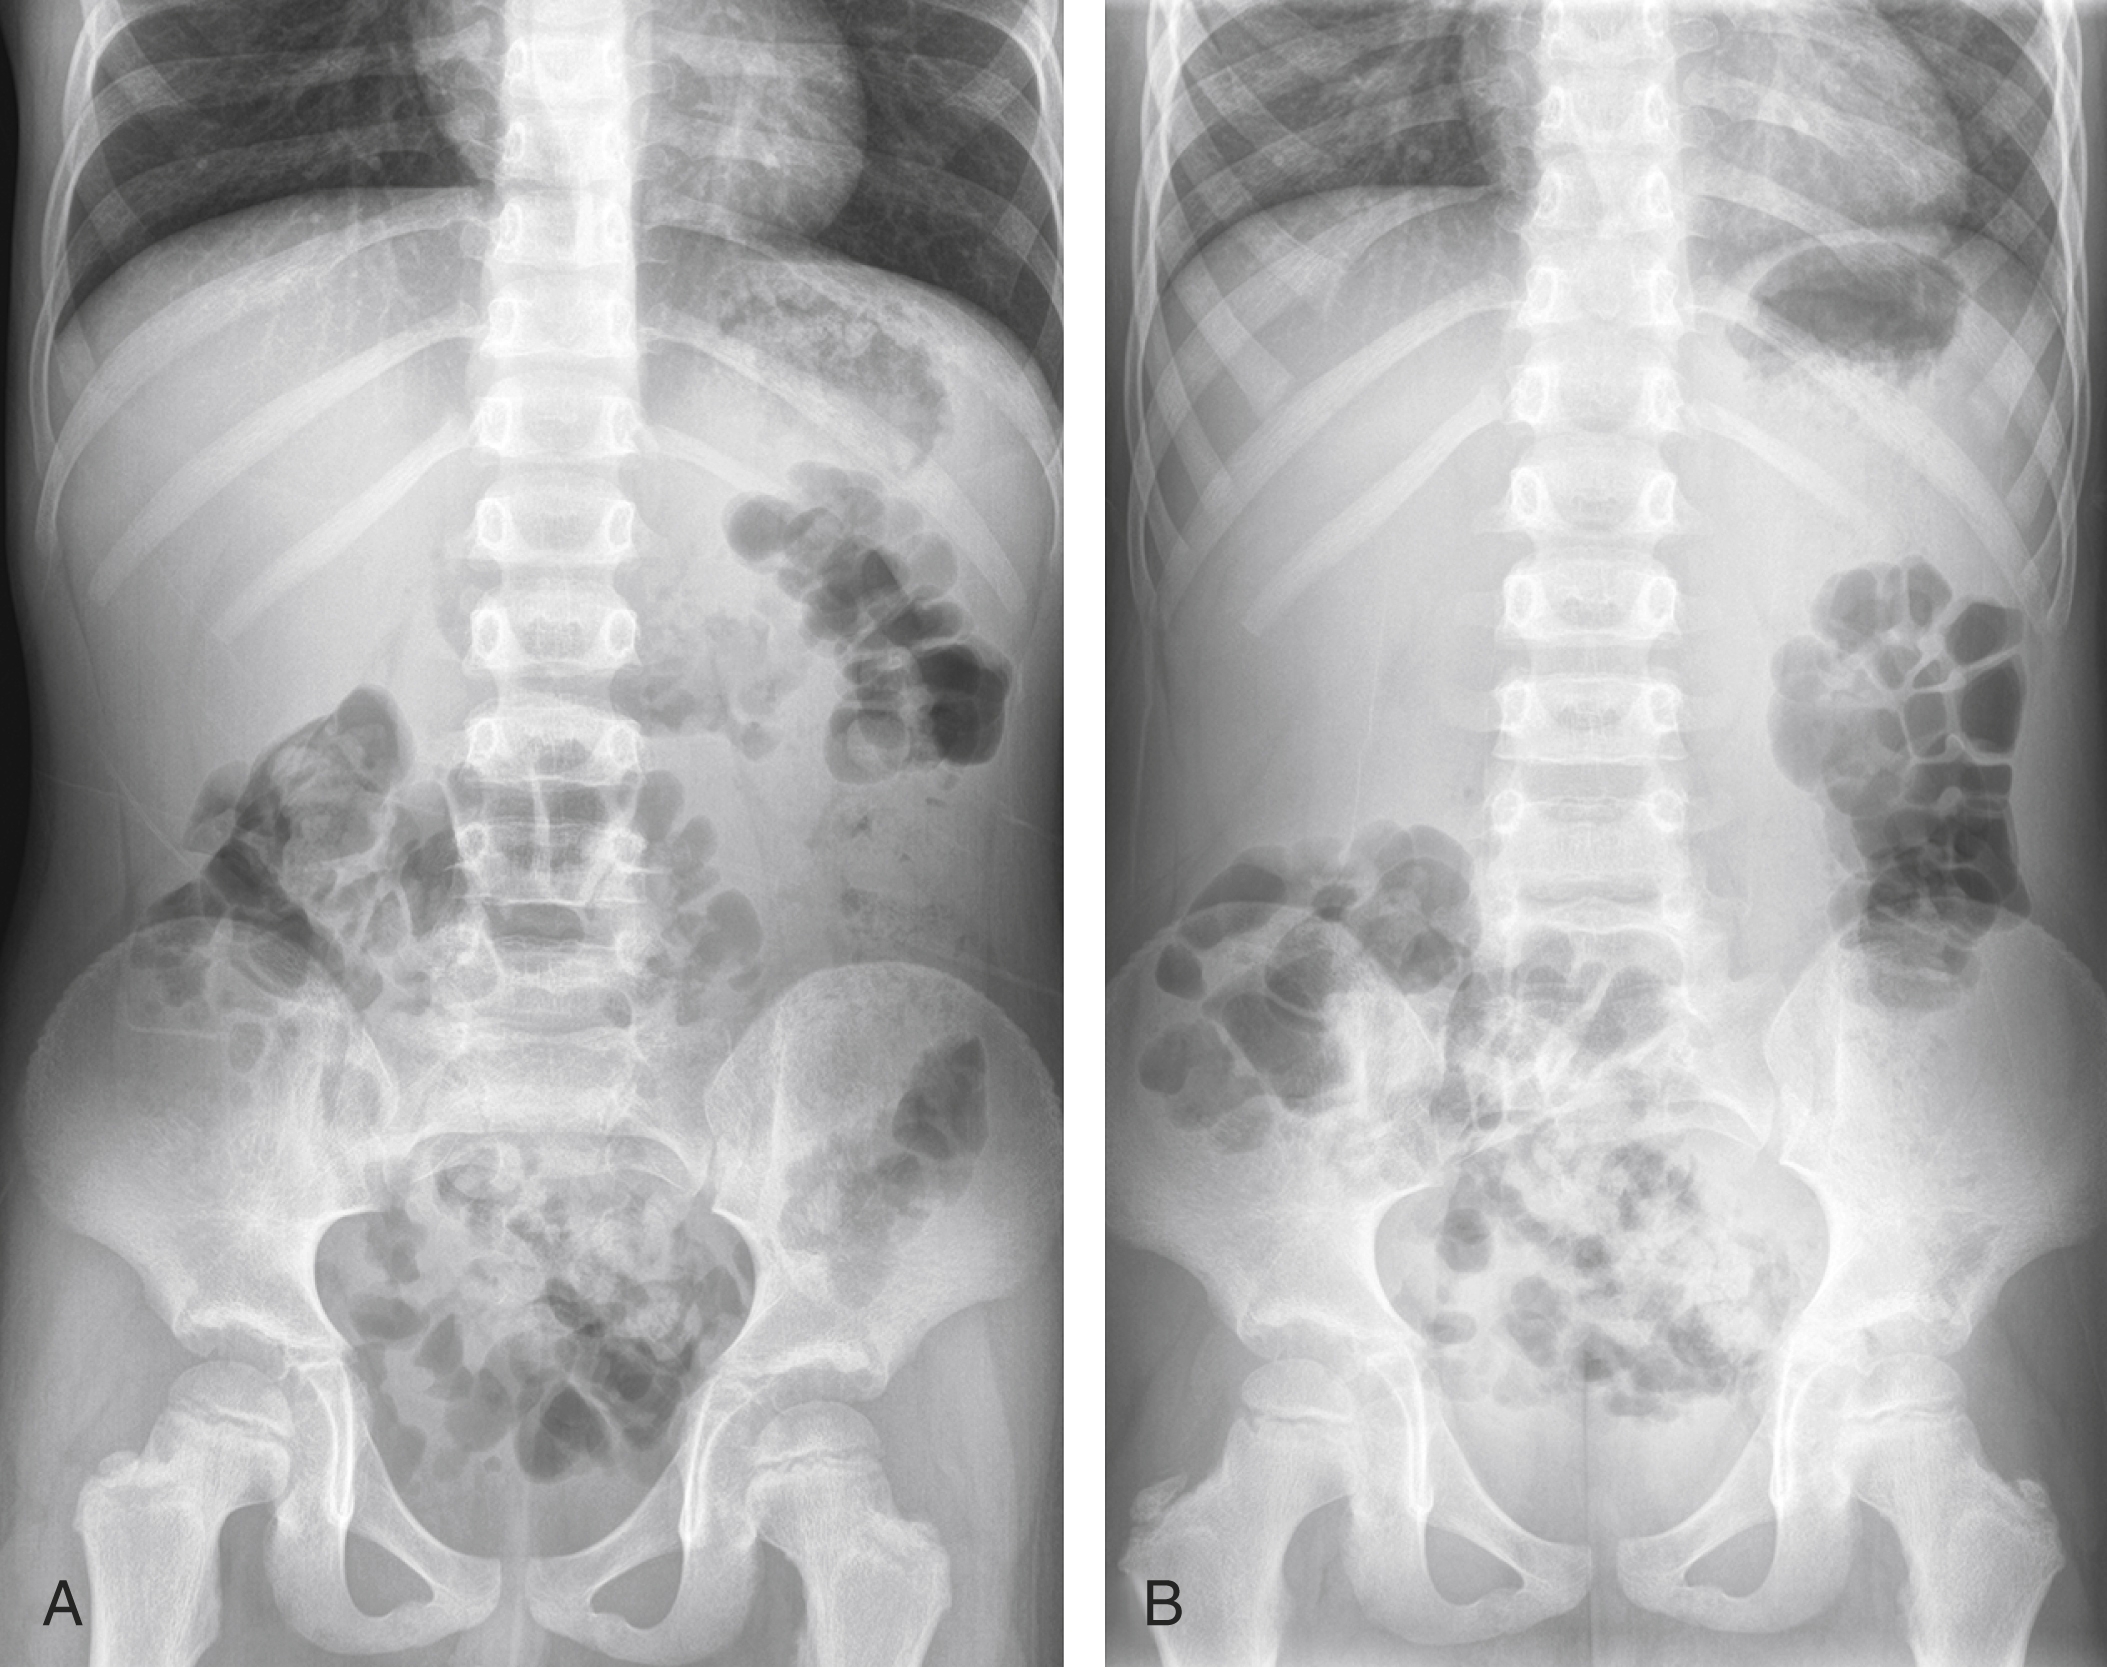

The nonobstructive bowel gas pattern appears as a normal arrangement of gas bubbles within the intestines. It shows that the intestines are functioning properly and that there are no blockages or abnormalities that could cause digestive issues.

In some cases, a nonobstructive bowel gas pattern may be seen in patients who are experiencing symptoms like bloating or abdominal pain. While this finding is reassuring, it’s essential for healthcare providers to consider other factors and conduct further tests if needed to determine the root cause of these symptoms.